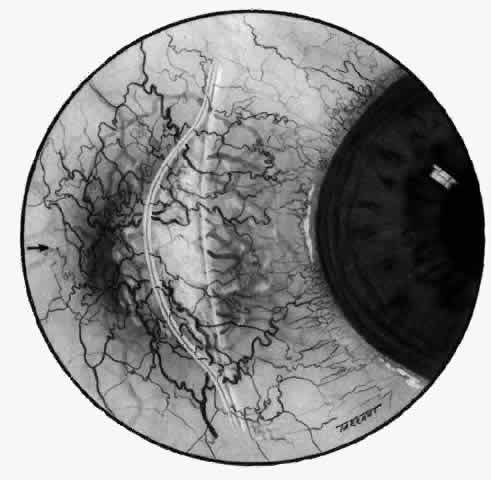

With the increasing use of anterior segment fluorescein angiography in the early detection of severe necrotizing disease of the sclera, it is necessary to have an understanding of the normal anatomy of the vasculature of the anterior segment of the eye.3–5 The blood supply to this region is enormous, being derived from the anterior ciliary arteries, but with extensive collateral arterial anastomoses to the posterior ciliary arteries at the root of the iris (Fig. 1). The anterior system is readily visible with the slit lamp and by anterior segment fluorescein angiography, especially if the eye is inflamed, and its recognition is of vital importance in the differentiation of episcleral and scleral conditions. The separation and displacement of these vascular layers give the most important clinical clues to the site and, hence, the severity of the inflammation. On slit lamp examination, three layers of vessels are readily visible. The conjunctival plexus, which is the most superficial layer of vessels, can be moved over the underlying structures. The superficial episcleral capillary plexus (Fig. 2) is a radially arranged series of vessels lying within the parietal layer of Tenon's capsule. The vessels in this layer anastomose at the limbus with the conjunctival vessels, with other members of the same plexus, and with the deep plexus. The deep episcleral capillary network (see Fig. 2) is closely applied to the sclera in the visceral layer of Tenon's capsule. The vessels anastomose freely with each other, forming a syncytium. The large vessels to and from the intrascleral plexus traverse the episclera near the insertions of the muscles. The conjunctival and superficial episcleral vessels can be blanched with 1:1000 epinephrine or 10% phenylephrine, but the deep vessels are affected slightly. This is of considerable assistance when attempting to differentiate deep and superficial inflammation.

Fig. 2. The normal relationships of the capillary networks that can be seen with the slit lamp are a conjunctival (easily mobile) network, a superficial episcleral network in the parietal layer of Tenon's capsule, and a deep episcleral plexus closely applied to the sclera. These relationships are much more obvious in inflamed eyes (see Figs. 13, 14, and 30). (Watson PG, Hayreh S, Awdry P: Episcleritis and scleritis. Br J Ophthalmol 52(3):278– 279, 1968)